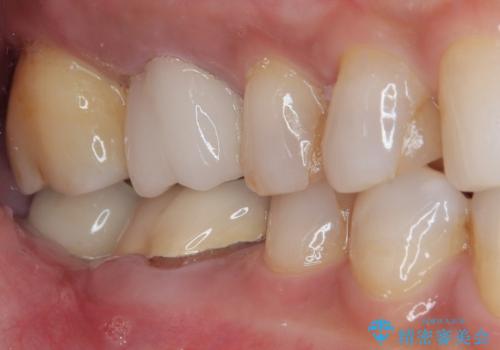

放置した奥歯 部分矯正を併用したインプラント補綴治療

理想的な咬み合わせに改善した上で、インプラント補綴治療を行うこととしました。

部分矯正を行ったこと治療期間は長くなりましたが、違和感のない咬み合わせを達成することができました。